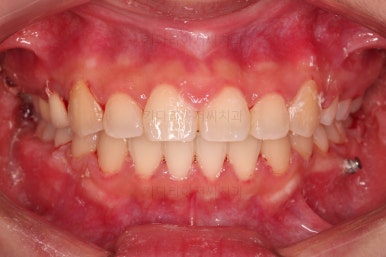

초진 시 입안의 모습을 보실게요.

결국은 앞니 사이에 틈이 생겼기 때문에 이같은 문제점을 인지하시고 내원하셨던거죠.

환자분 : "임플란트 하기 전에 앞니 틈도 모으고 싶어요."

이번 환자분의 경우는 치아 결손 부위의 잇몸뼈도 양호했고 공간도 그리 크진 않았으며 윗니는 갯수가 1개 부족해도 교합을 맞추는데 문제가 거의 없기 때문에 시간이 좀 더 들더라도 임플란트 없이 앞니 사이 틈과 결손부위 틈새를 모아보기로 했어요.

다만 치아 사이 틈새가 벙러져 미적으로 좋지 못한 상황이었고요.